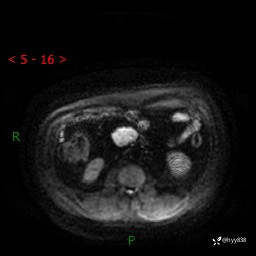

MRI(T1WI+T2WIfs+DWI)

增强